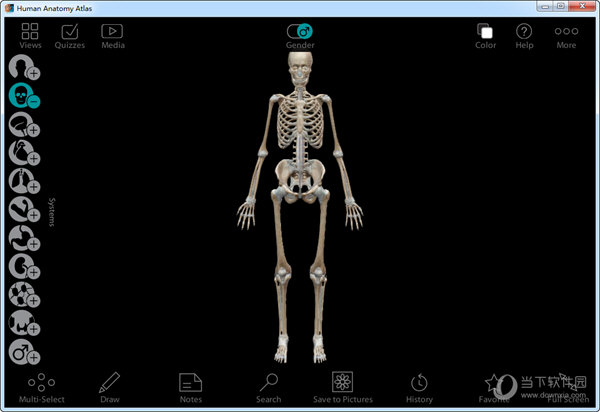

1、提供人体模型查看,可以显示三维模型

2、可以使用鼠标移动模型,可以旋转模型

3、提供简单的器官添加方式,在软件左侧就可以找到常用的器官

1、通过左侧的这些功能可以针对人体的神经、骨骼、肌肉进行分层查看学习。